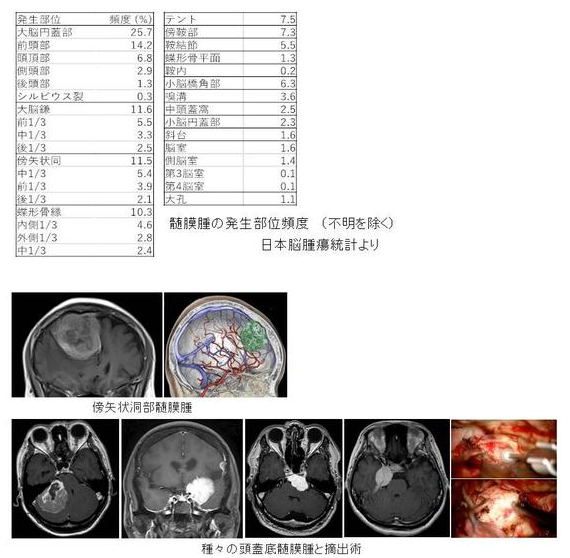

日本看?。耗X膜瘤日本醫(yī)院介紹--圣瑪麗安娜醫(yī)院